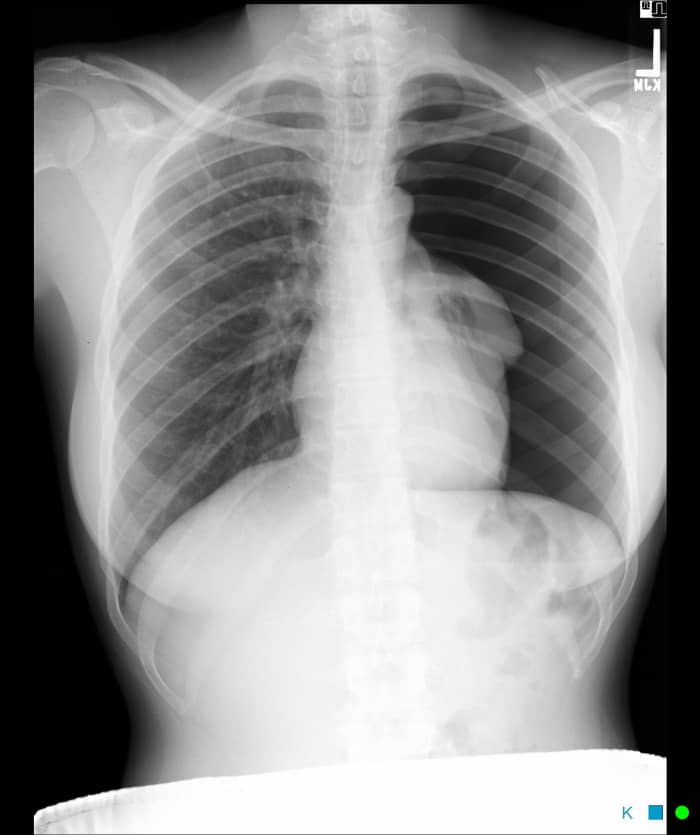

Креативные рентген-снимки рук с изображением сердечка

Раздел: Необычные решения